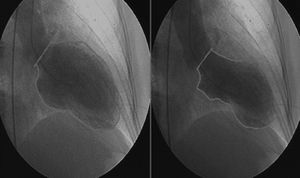

Urgent cardiac catheterization, performed under anticoagulation and dual antiplatelet therapy with aspirin and clopidogrel showed normal coronary arteries and no vasospasm. Ventriculography showed akinesia with apical ballooning and moderate global systolic dysfunction (ejection fraction 42%) (Figure 3). Biomarkers of myocardial necrosis were elevated (peak troponin I 6.45ng/ml and CK-MB mass 27.1μg/dl, with total CK 248μg/dl). C-reactive protein (CRP) was 0.2mg/dl. During hospital stay she was free of chest pain and developed generalized T-wave inversion on the ECG (Figure 4), accompanied by progressive recovery of the LV wall motion abnormalities. Therapy was maintained with dual antiplatelets, anticoagulation, angiotensin-converting enzyme inhibitors (captopril 6.25mg every 8h) and statins (atorvastatin 10mg/day). Beta-blockers were not tolerated due to symptomatic bradycardia.